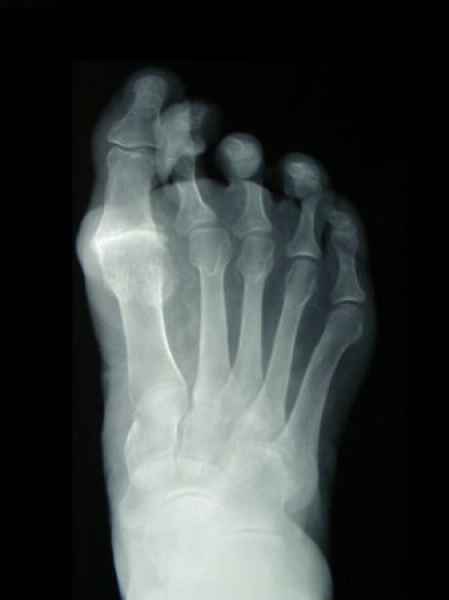

El pie es el órgano distintivo y característico de la especie humana, la única criatura que marcha erguida. El pie es una muy compleja estructura de arquitectura perfecta, adaptado a su función de apoyo, traslación, salto, con una riquísima sensibilidad que le permite detectar las más leves imperfecciones del suelo para estabilizar la marcha.

La marcha no solo es característica de la especie humana sino también de cada persona, y más aún varía según el estado de ánimo del momento. Una patología en los pies, se traduce en el rostro, en el ánimo, en el psiquismo. No sólo el dolor produce estos efectos, también un pie deformado o poco estético. En nuestra sociedad, la estética constituye un valor muy apreciado y estas alteraciones causan vergüenza fundamentalmente en las mujeres, que esconden en la playa sus pies en la arena y no pueden usar calzados elegantes.

Tanto la estructura del pie como su funcionalismo que es la marcha, pueden ser asiento y manifestación respectivamente de alteraciones locales ó sistémicas, por lo que su cuidadoso examen resulta de extrema utilidad diagnóstica.